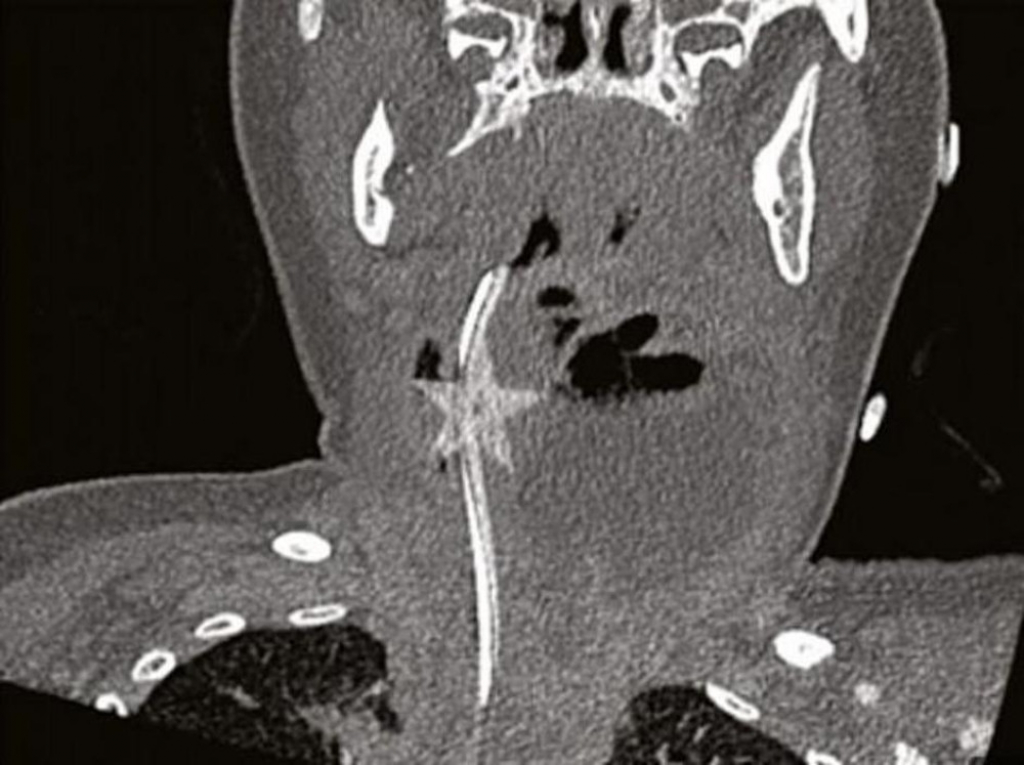

- Dijagnostikovali su joj bronhiolitis te je sledeća tri dana dobijala terapiju, a potom su je opet poslali kući. Međutim, vratila se ponovo šest dana sa istim simptomima, pa su odlučili da joj snime vrat - pišu u časopisu doktori Paul Heyworth i Ryan Shulman. Tek tada otkrili su što joj je - u grlu se stvorio apsces, gnojna nakupina oko zvezde petokrake. Devojčicu su hitno odveli na operaciju kako bi uklonili zvezdu i gnoj, a malena se potom dobro oporavila.